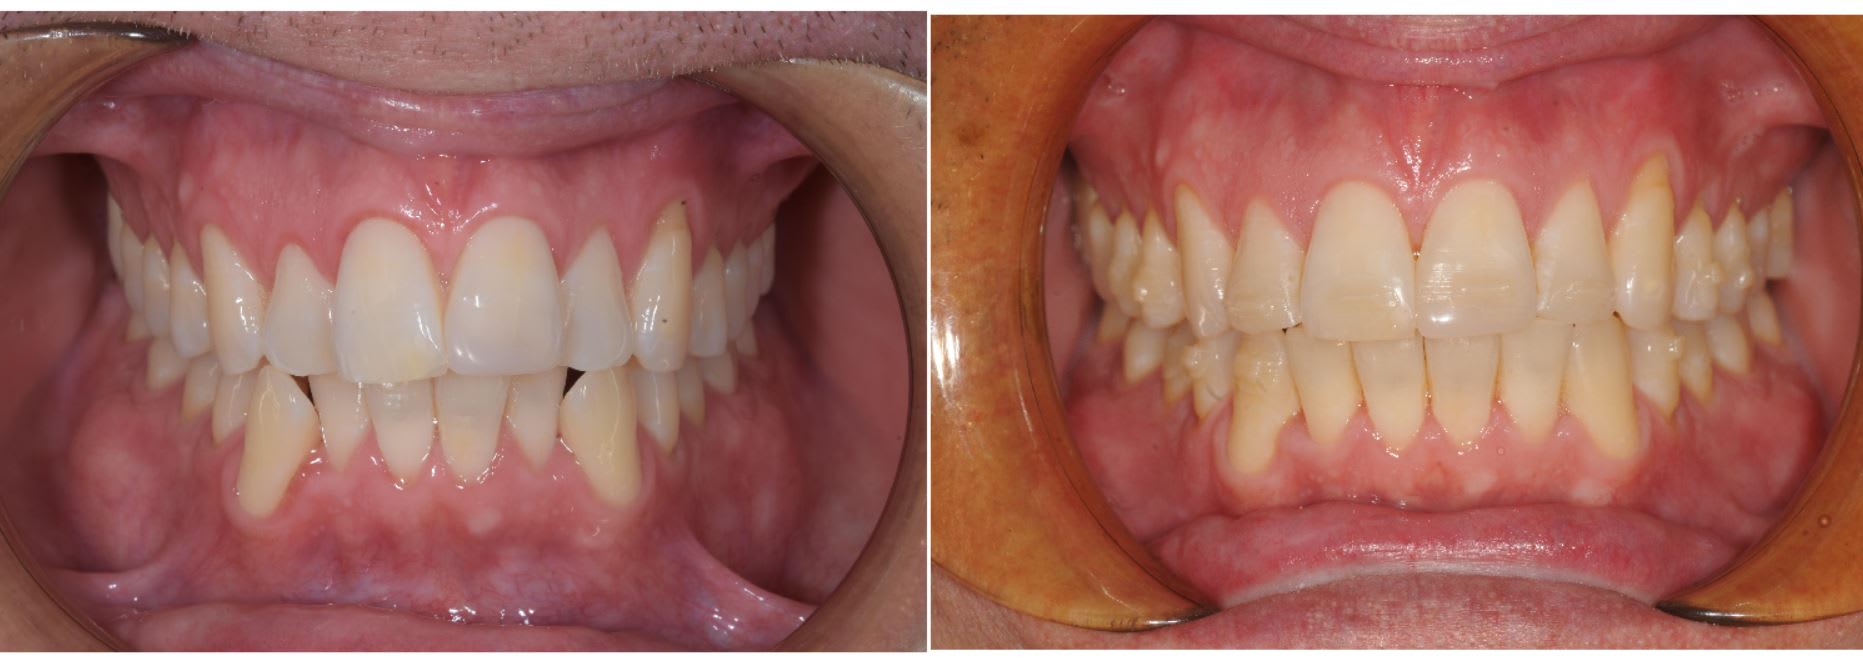

Un bon exemple d'utilisation aligneur maison en orthodontie.

On à commencé avec de la 2D pendant quatre mois, puis trois mois avec aligneur.

Là c'est un exemple classique d'une utilisation qui devient très intéressante quand vous faite in-house car ça permet d'être très réactif ( aligneur près en deux jours ).

Le patient ne venait que pour de brève durée sur Phnom Penh, donc pas possible d'avoir les gouttières à temps en passant par un lab extérieur.